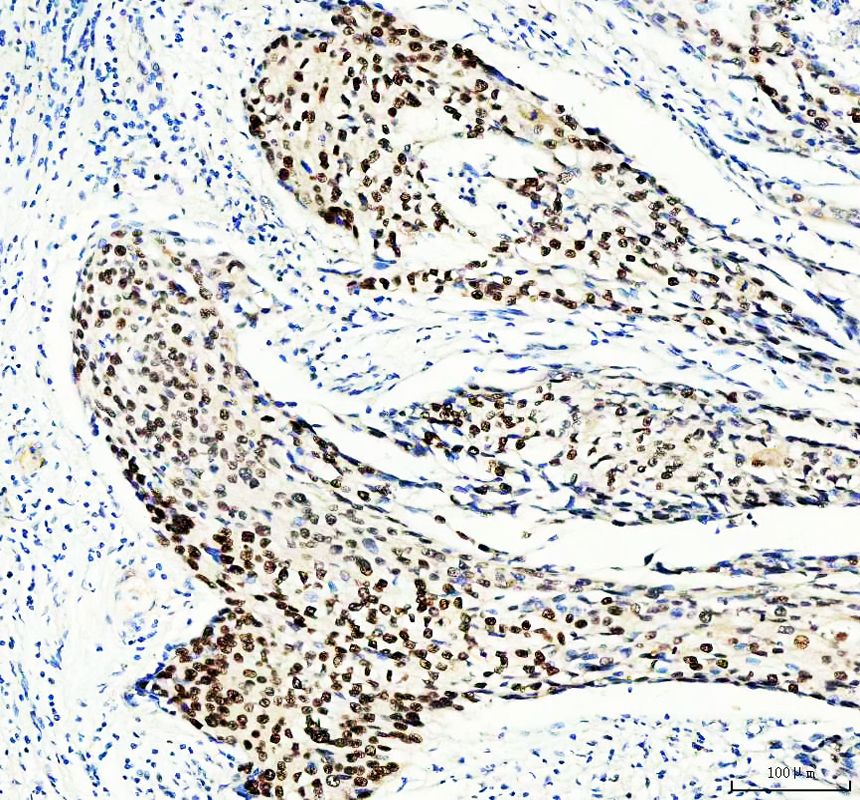

IHC analysis of MCM3 using anti-MCM3 antibody (BA2186).

MCM3 was detected in a paraffin-embedded section of human breast cancer tissue. The tissue section was incubated with rabbit anti-MCM3 Antibody (BA2186) at a dilution of 1:200 and developed using HRP Conjugated Rabbit IgG Super Vision Assay Kit (Catalog # SV0002) with DAB (Catalog # AR1027) as the chromogen.